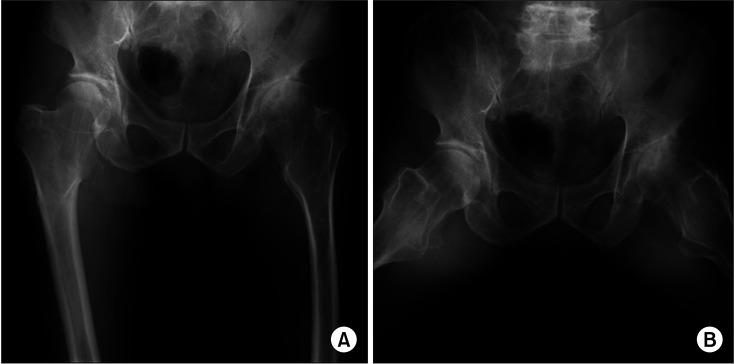

Hereditary multiple exostoses (HME) is an autosomal dominant disorder. The lesion in the proximal femoral metaphysis can bring about hip dysplasia and subsequent degenerative arthritis. Due to its rare prevalence, there have been a few case reports of total hip arthroplasty (THA) for osteoarthritis secondary to HME. The aim of this study was to report mid- to long-term outcomes of THA in HME patients and discuss special considerations that should be taken into account during surgery.

We retrospectively evaluated the clinical and radiological results of THA for osteoarthritis secondary to HME in 11 hips of 9 patients after a minimum follow-up of 5 years (mean, 9.9 years). There were 3 men (3 hips) and 6 women (8 hips), with a mean age of 53.6 years (range, 46.8-58 years) at the index surgery in this study. Harris hip score (HHS) was used for clinical outcome assessment, and radiologically, implant stability, radiolucent lines, liner wear, and any sign of osteolysis or implant loosening were evaluated. Postoperative complications including infection, deep vein thrombosis, and dislocations were also investigated.

Despite the several surgical considerations, the mid- to long-term clinical and radiological outcomes of THA in HME patients were satisfactory. The abnormal, wide mediolateral diameter of the proximal metaphysis should be considered in selecting and inserting the stem with adequate anteversion. Leg length discrepancy was also common, so teleradiographs should be obtained before surgery. Intraoperative leg length evaluation might be difficult due to the morphologic changes in the proximal femur after mass excision and individual bone length differences.